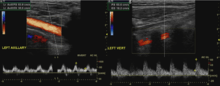

In medicine, subclavian steal syndrome (SSS), also called subclavian steal phenomenon or subclavian steal steno-occlusive disease, is a constellation of signs and symptoms that arise from retrograde (reversed) blood flow in the vertebral artery or the internal thoracic artery, due to a proximal stenosis (narrowing) and/or occlusion of the subclavian artery. The arm may be supplied by blood flowing in a retrograde direction down the vertebral artery at the expense of the vertebrobasilar circulation. This is called the subclavian steal. It is more severe than typical vertebrobasilar insufficiency.

SSS results when the short low resistance path (along the subclavian artery) becomes a high resistance path (due to narrowing) and blood flows around the narrowing via the arteries that supply the brain (left and right vertebral artery, left and right internal carotid artery). The blood flow from the brain to the upper limb in SSS is considered to be stolen as it is blood flow the brain must do without. This is because of collateral vessels.

In SSS a reduced quantity of blood flows through the proximal subclavian artery. As a result, blood travels up one of the other blood vessels to the brain (the other vertebral or the carotids), reaches the basilar artery or goes around the cerebral arterial circle and descends via the (contralateral) vertebral artery to the subclavian (with the proximal blockage) and feeds blood to the distal subclavian artery (which supplies the upper limb and shoulder).